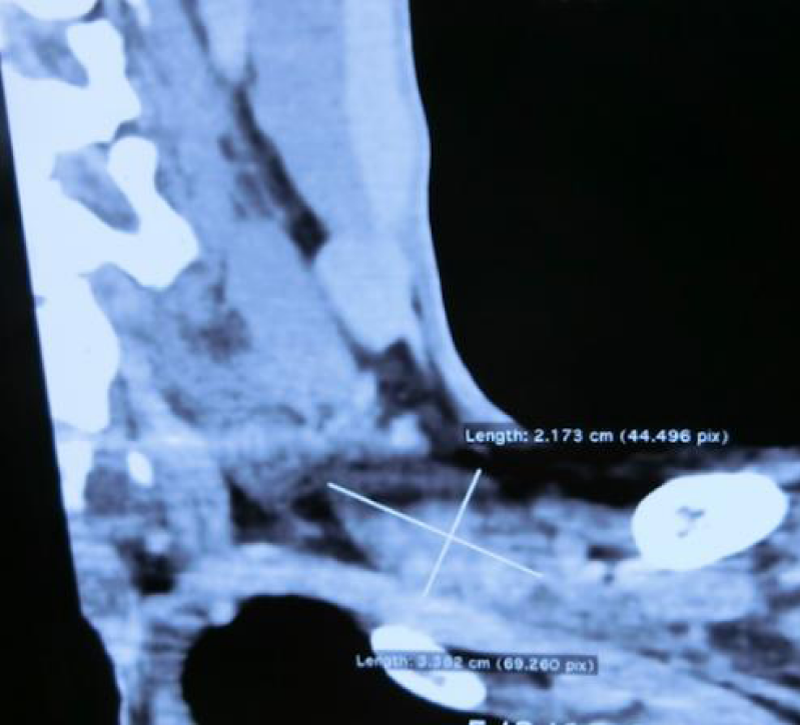

A 39 year-old lady had cancer of right breast. There was an incidental finding of an axillary mass during lumpectomy of right breast and sentinel lymph node biopsy surgery. Patient was asymptomatic. She was then referred to our team for further management. MRI and biopsy confirmed the mass was a brachial plexus schwannoma (Figures 11,12). Deltopectoral approach was used in this case (Figure 13). There was a 2.0x2.8x2.3cm lesion located at posterior cord of right brachial. Enucleation was performed. There was no neurological deficit after the operation.